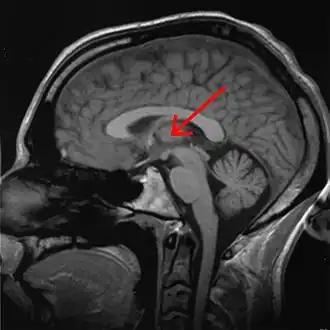

The effects of sleep deprivation on cognitive performance have been studied through the use of parametric visual attention tasks. Functional magnetic resonance imaging of participants' brains who were involved in ball-tracking tasks of various difficulty levels were obtained. These images were taken during rested wakefulness and again after one night of sleep deprivation. The thalamus is more highly activated when accompanied by sleep deprivation—than when the subject is in a state of rested wakefulness. Contrarily, the thalamus is more highly activated during difficult tasks accompanied by rested wakefulness, but not during a state of sleep deprivation. Researchers propose that the thalamic resources, which are normally activated during difficult tasks, are being activated in an attempt to maintain alertness during states of sleep deprivation. An increase in thalamic activation is related to a decrease in the parietal, prefrontal and cingulate cortex activation, resulting in the overall impairment of attentional networks, which are necessary for visuospatial attention performance.[12]

fMRI scans following brief sleep deprivation (24 hours or less) show increases in thalamic activation. Verbal working memory tasks normally cause increases in left temporal lobe activity. After 35 hours come noted decreases in temporal lobe activation and increases in parietal lobe activation.[42]